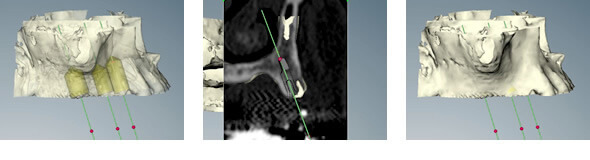

サージカルテンプレートを用いたフラップレスで、確実でより安全に

インプラント

CTスキャンデータ、3Dシミュレーションソフトを使いインプラントの埋める位置を確認します。

そのデータをもとに、精巧なノーベルガイドを用いたサージカルテンプレートを作製。シミュレーションにより算出したインプラントの埋入の位置や角度が正確にわかりますので、安全で確実な手術ができます。

オペはこの、サージカルテンプレートを歯肉へ装着して、一部分に小さな穴を開けてインプラントを埋入します。

ほとんどの歯肉をきりませんので術後の腫れ・痛みをおさえることができます。